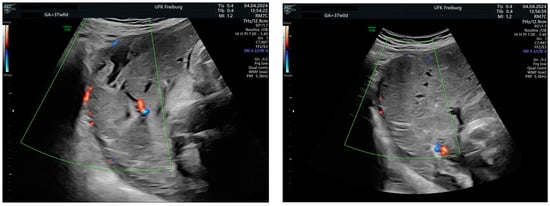

Sonographic findings (Figure 4):

Figure 4.

shows suspected placenta increta with dehiscence in the area of scar tissue from the previous uterotomy.